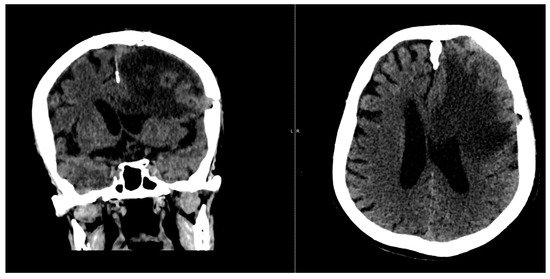

The postoperative course was favorable, with significant neurological improvement observed (Figure 5 and Figure 6).

Figure 5. CT scan conducted 7 days post-surgery.

Figure 6. CT scan conducted 14 days after the surgery.